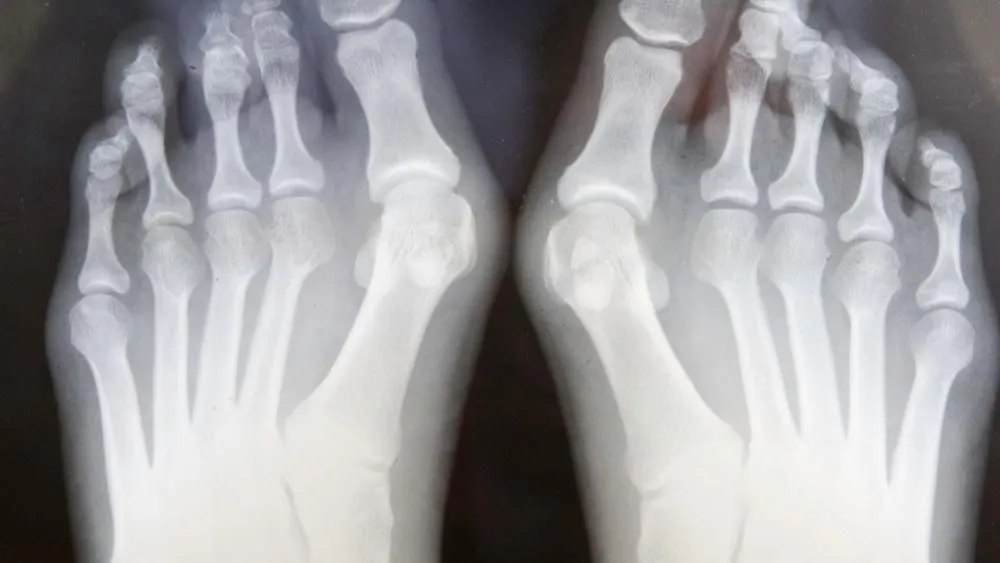

Ortopeda to najlepszy specjalista, do którego warto się udać w przypadku haluksów. Posiada on odpowiednie kwalifikacje oraz umiejętności, aby skutecznie ocenić stan stóp pacjenta. Ortopeda przeprowadza kompleksową diagnostykę, w tym zleca badania obrazowe, takie jak zdjęcia RTG, co pozwala na dokładną ocenę deformacji.

W trakcie wizyty ortopeda może zlecić różne badania diagnostyczne, aby dokładnie ocenić stan zdrowia stóp. Najczęściej wykonywane badania to zdjęcia RTG, które pozwalają zobaczyć stopień deformacji oraz ocenić, jak zmiany wpływają na układ kostno-stawowy. W niektórych przypadkach lekarz może również przeprowadzić badanie fizykalne, aby sprawdzić zakres ruchu w stawach oraz zidentyfikować miejsca bólu.

- RTG stopy – badanie obrazowe, które pozwala ocenić stopień zaawansowania deformacji oraz stan kości.